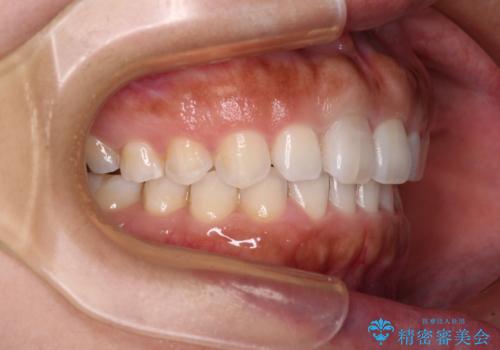

隙間の空いた前歯を閉じたい インビザライン矯正

- 前歯の隙間を気にして来院された患者様です。

隙間、捻転ともに軽微でありましたが、下顎前歯の突き上げにより隙間ができていたため、インビザラインを用いて咬み合わせを改善しながら前歯の歯列を整えていくこととしました。

当初は1年程度で終えられると思いましたが、治療途中から装着時間が短くなったり、来院間隔が長期になったりとし、結果として4年半以上の治療期間となりました。

治療途中に上顎前歯は失活してしまいましたが、変色が顕著ではないため、経過を見ていくこととなりました。